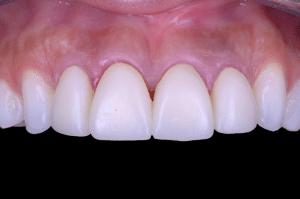

Fig 1.

Particulièrement en fin de séance de prise d’empreinte, et d’une façon plus générale, l’élimination du ciment temporaire en excès après le scellement de couronnes provisoires solidarisées ou d’un bridge est un enjeu capital. En effet, la cicatrisation parodontale sera directement influencée par le retrait de tout le ciment débordant.